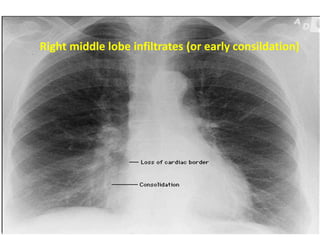

1- Determine location :

Loss of heart borders or of the contour of the diaphragm

E.g. : Right middle lobe consolidation blurs the heart

border

Right middle lobe infiltrates (or early consildation)